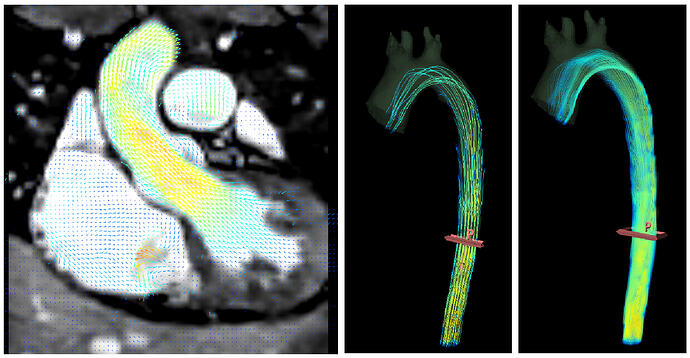

- Flow fields (vxyz) - such as 4D flow MRI

4D flow MRI

Some recent MRI systems allow real-time recording of 4D+t flow images, which store a 3D velocity vector at each voxel position, for tens of timepoints in the cardiac cycle. Previously, the only way to save such data sets was to save multiple 4D volumes in a zip file. These can now be saved as 5D vector field files.